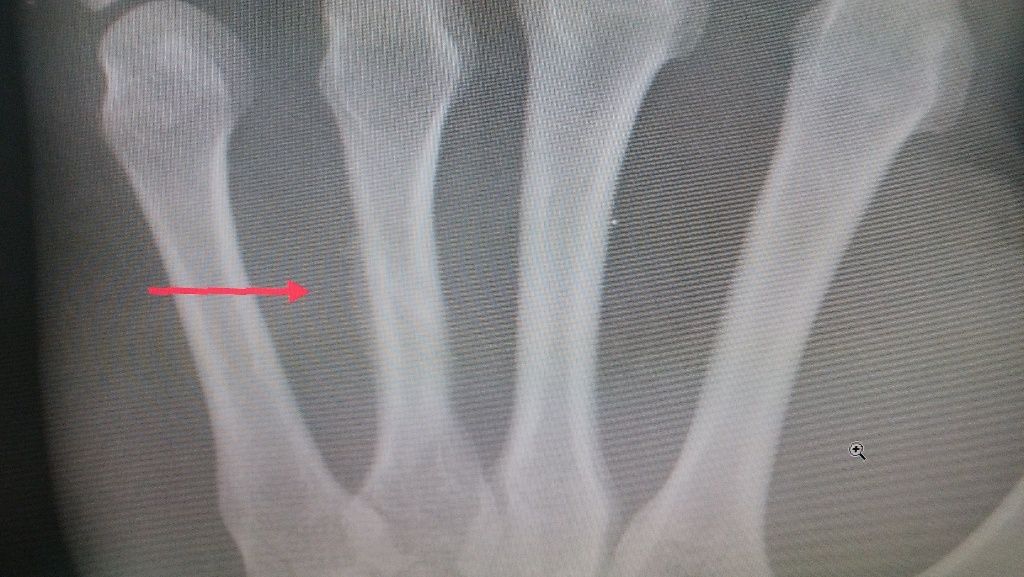

転位骨折 4週で 癒合

イメージ 2